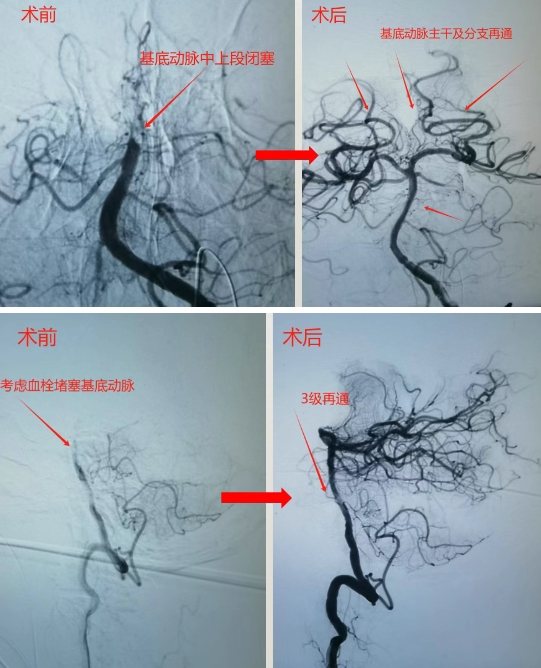

56岁的沙先生,是一名远洋渔船作业人员,工友发现意识不清10余小时。既往甲亢,房颤病史。入院查体深昏迷,刺痛无反应,四肢无活动,双侧病理征阳性,头颅CT提示未见脑内出血。入院诊断:急性基底动脉闭塞,脑干梗塞,房颤。实施术式:脑血管造影,基底动脉机械取栓,脑动脉导管溶栓手术�术中造影可见基底动脉闭塞,考虑血栓脱落导致。不及时开通,致死的可能性大�进一步采取支架及取栓导管抽吸取栓,微导管动脉内溶栓手术方式,及时开通了基底动脉主干及主要分支�患者术后刺痛反应较前改善,浅昏迷。经气管切开,脱水,改善脑循环等积极治疗后,病情稳定后转回当地樱花动�